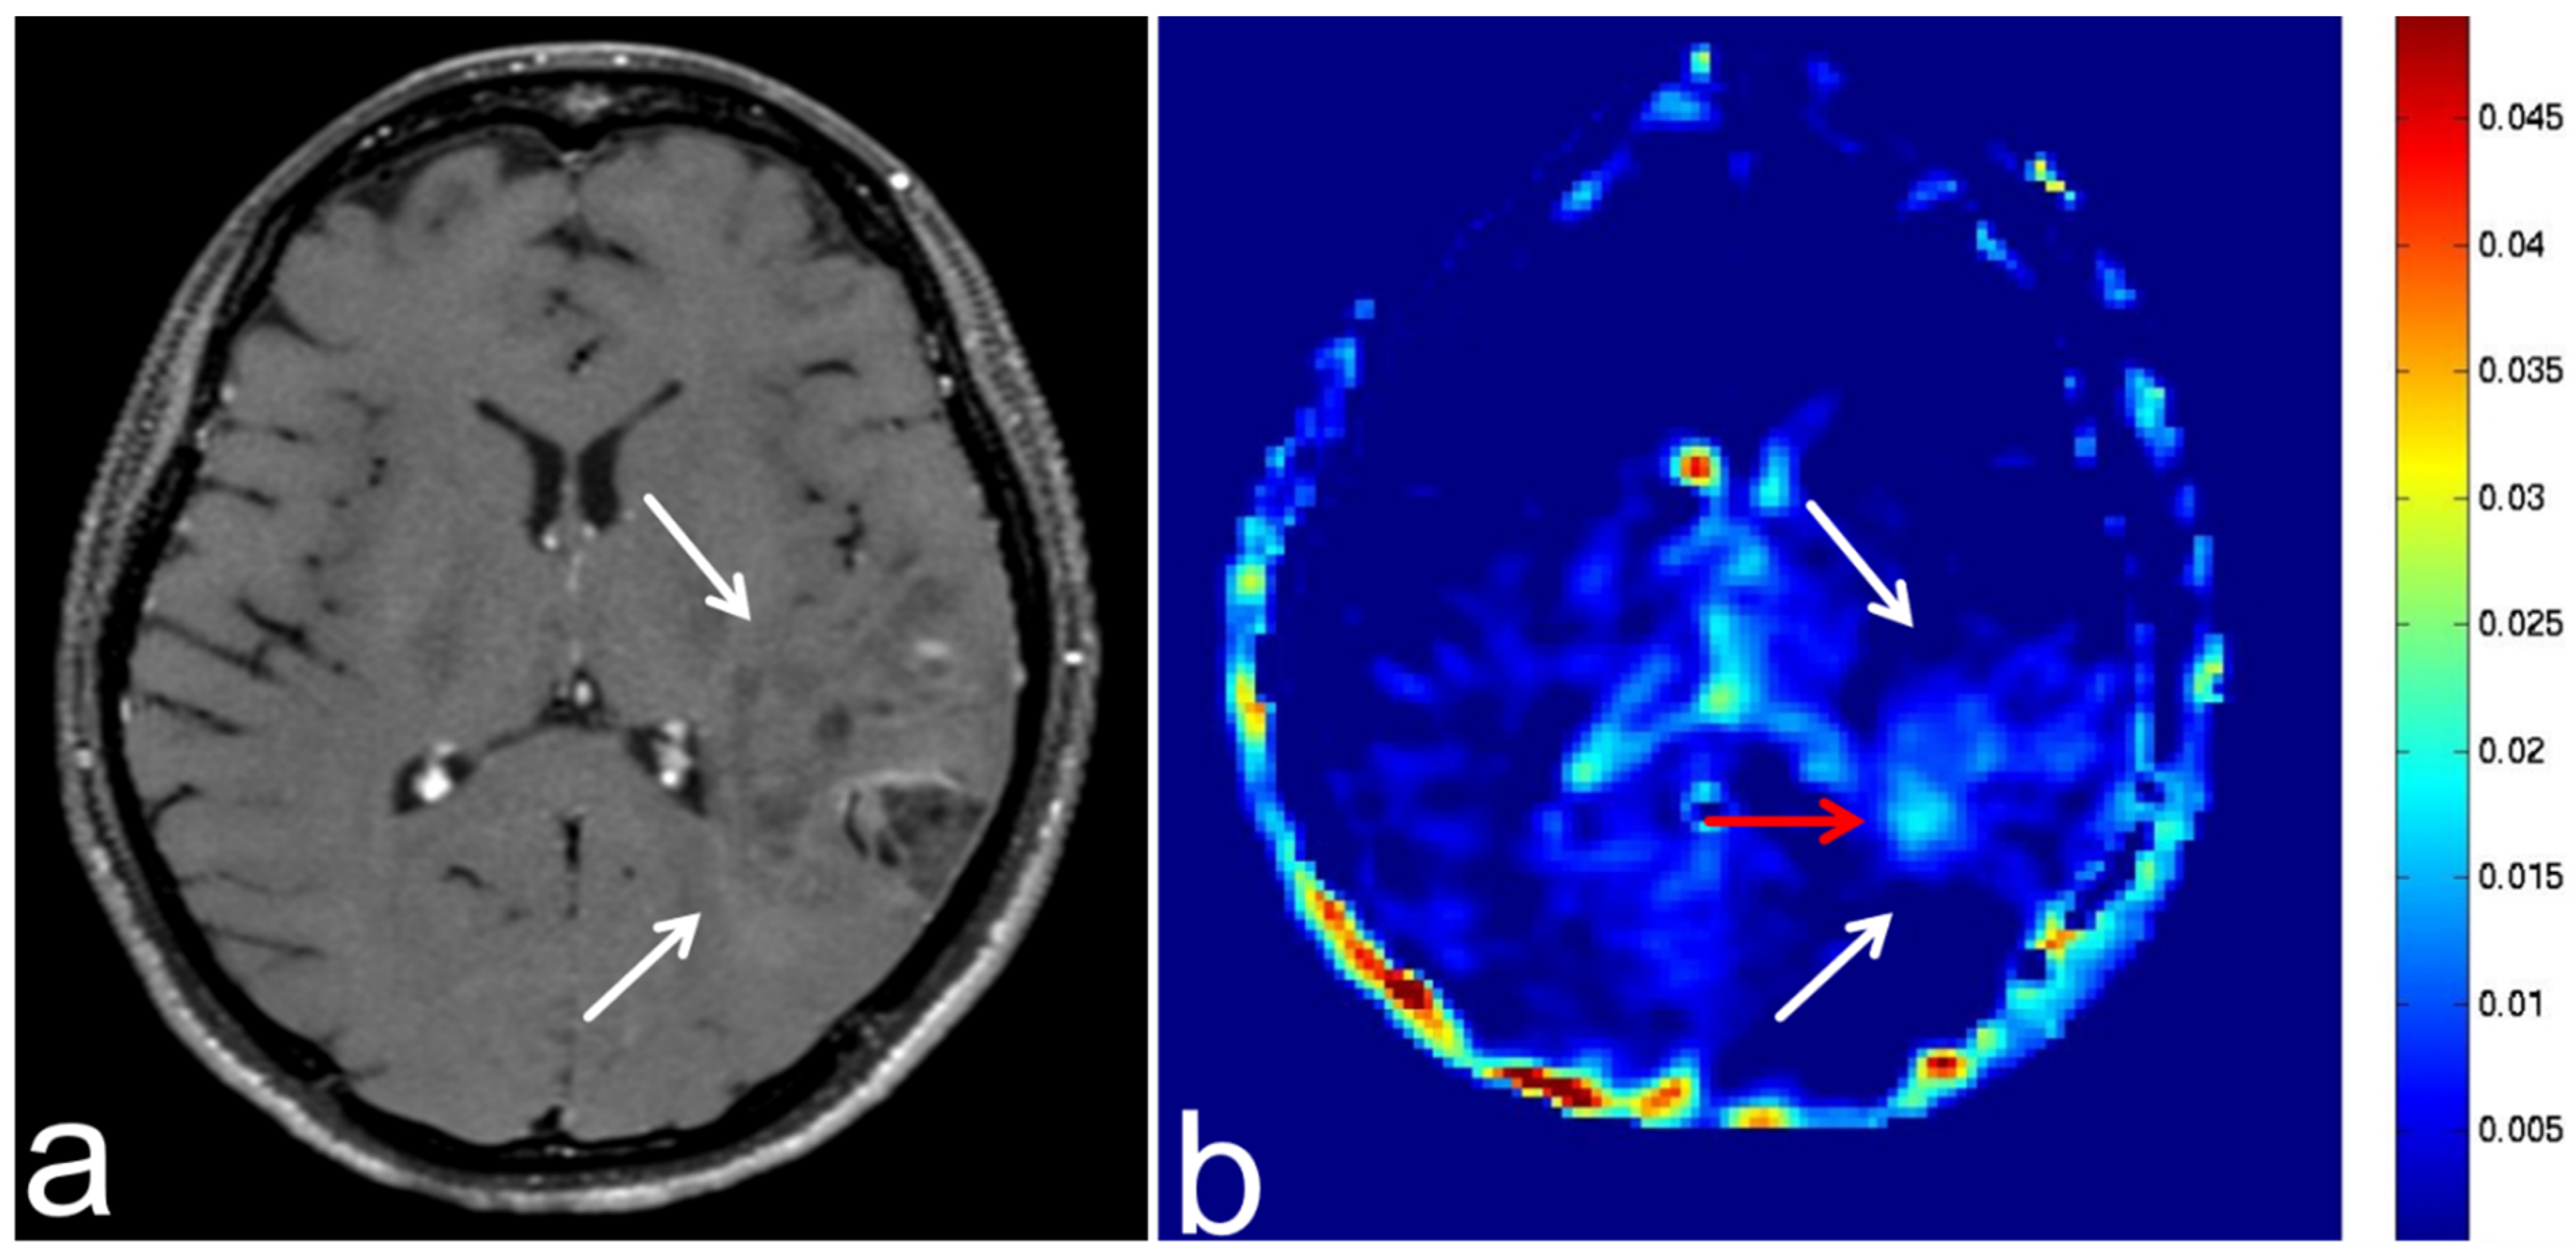

5.4. Malignant Lymphoma